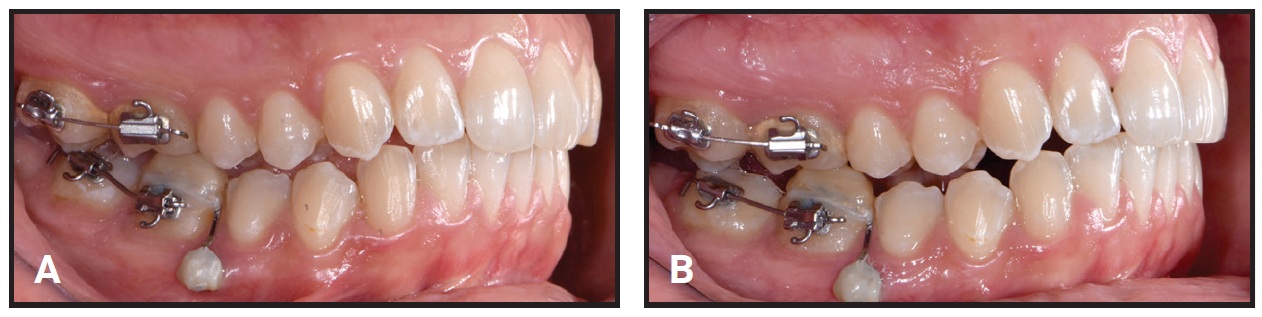

After two months of treatment, the scissor bite had not improved, and the patient complained of difficulty in fitting the aligners over the posterior regions of both arches (Fig. 3).

Fig. 3 Scissor bite unimproved after two months of treatment.

With the patient’s consent, we decided to cut off the remaining aligner trays on the right side in both arches and to end the first phase of therapy, postponing the correction of the scissor bite to the refinement stage. The patient was instructed to wear each pair of modified aligners for 10 days. This first treatment phase lasted four months and 20 days (Fig. 4). The crowding and malalignment were resolved, gingival exposure in smiling was reduced, and the midlines were partially centered.